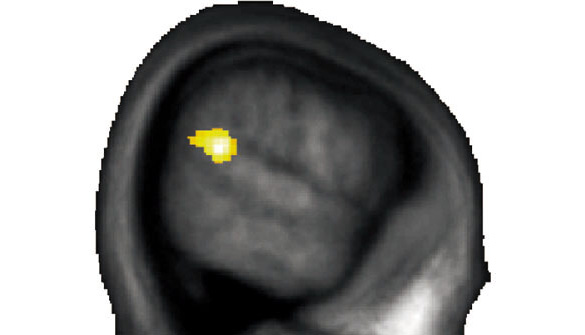

Das Ziel der Studie war jedoch herauszufinden, warum es solche Unterschiede gibt. Frühere Studien legten dar, dass eine bestimmte Hirnregion – die Übergangsregion zwischen dem Scheitel- und dem Schläfenlappen – mit der Fähigkeit zusammenhängt, sich in die Lage anderer Menschen hineinzuversetzen, um ihre Gefühle und Gedanken zu verstehen. Altruismus wiederum hängt mit dieser Fähigkeit wahrscheinlich eng zusammen. Daher vermuteten die Forschenden, dass individuelle Unterschiede in dieser Grenzregion mit unterschiedlichem altruistischen Verhalten zusammenhängen. Was laut Yosuke Morishima, Postdoktorand am Institut für Volkswirtschaftslehre der Universität Zürich, der Fall ist: «Personen, die sich altruistischer verhielten, wiesen auch mehr graue Hirnsubstanz in der Übergangsregion zwischen Scheitel- und Schläfenlappen auf.»

Während ihrer Entscheidungen zur Geldteilung zeigten die Studienteilnehmenden auch deutliche Unterschiede in ihrer Hirnaktivität. Bei egoistischen Personen ist die kleine Hirnregion hinter dem Ohr schon bei geringen Kosten einer altruistischen Handlung aktiv. Bei altruistischen Personen hingegen wird diese Hirnregion erst stärker aktiv, wenn diese Kosten bereits sehr hoch sind. Die Hirnregion ist folglich dann besonders stark aktiviert, wenn Menschen an die Grenzen ihrer Bereitschaft gelangen, altruistisch zu handeln. Weil zu diesem Zeitpunkt, so vermuten die Forschenden, die grösste Notwendigkeit besteht, den natürlichen Egozentrismus des Menschen durch Aktivierung dieser Hirnregion zu überwinden.